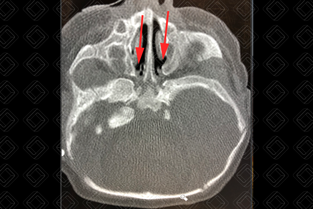

Texto alternativo para a imagem Créditos: Dra. Elazir Mota - Rio de Janeiro/RJ

Descrição da figura: Atresia coanal bilateral com componente membranoso obliterando o espaço entre a cavidade nasal e rinofaringe.

• O principal exame de imagem é a tomografia computadorizada de face para adequada avaliação da redução do espaço entre a parede medial do seio maxilar e vômer, e sua caracterização quanto ao tipo, cartilaginoso ou ósseo, e se acometimento é uni ou bilateral. Serve, ainda, como excelente método para avaliar outras anomalias de ouvido interno e face que podem estar associadas (figura acima).